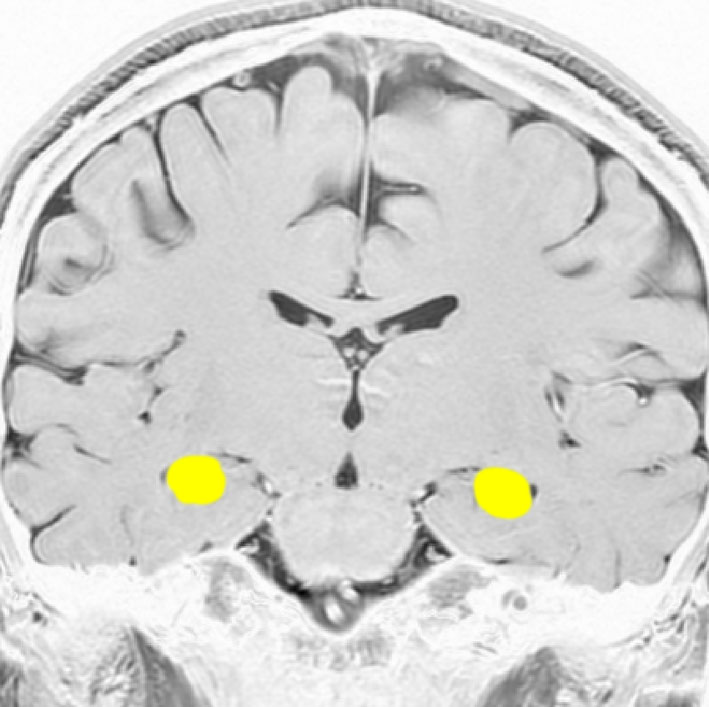

海馬

両側の側頭葉の内側にあり,学習,記憶,空間認識(spartial awareness。物体のある場所・大きさ・形・速さ・向き・物体同士の位置関係などを素早く正確に認知する能力)を司ります

記憶に関しては左側の海馬に優位性が大きいです

左の海馬を横から見たところです

記憶の中枢であり,この部位の機能低下は認知症を招きます

アルツハイマー病の原因ともなる部位です